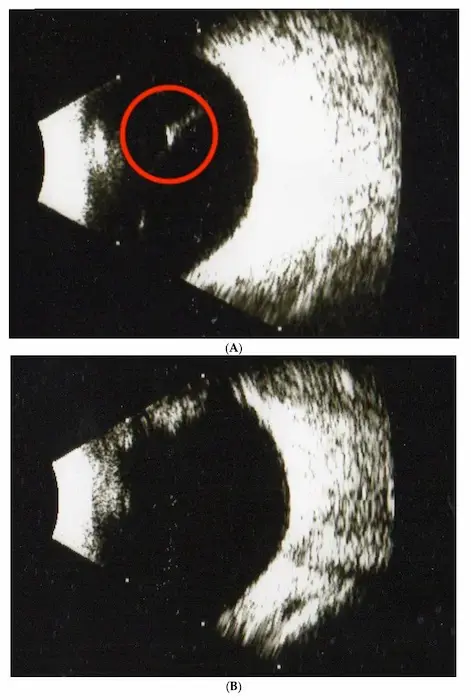

Here's a visualization of what the supplement did. On the top (A) is one individual before the study. The bottom (B) is them after 6 months of the supplement.